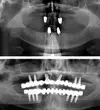

Implant tedavisi